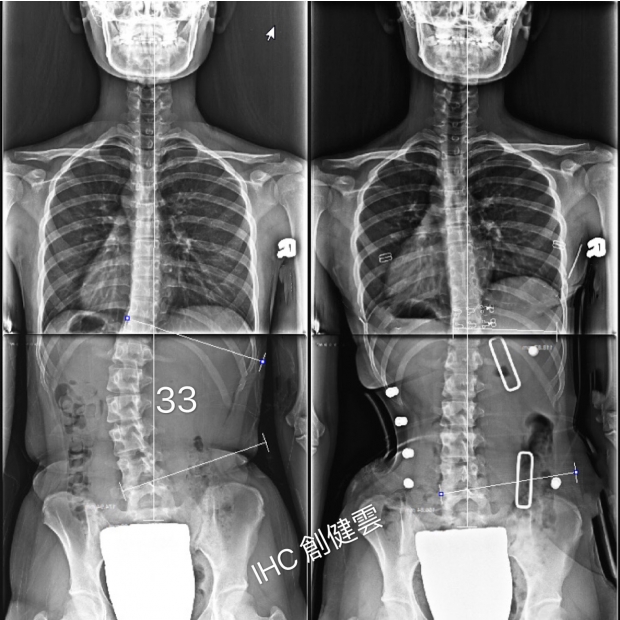

16歲C型脊椎側彎女孩

腰彎33度